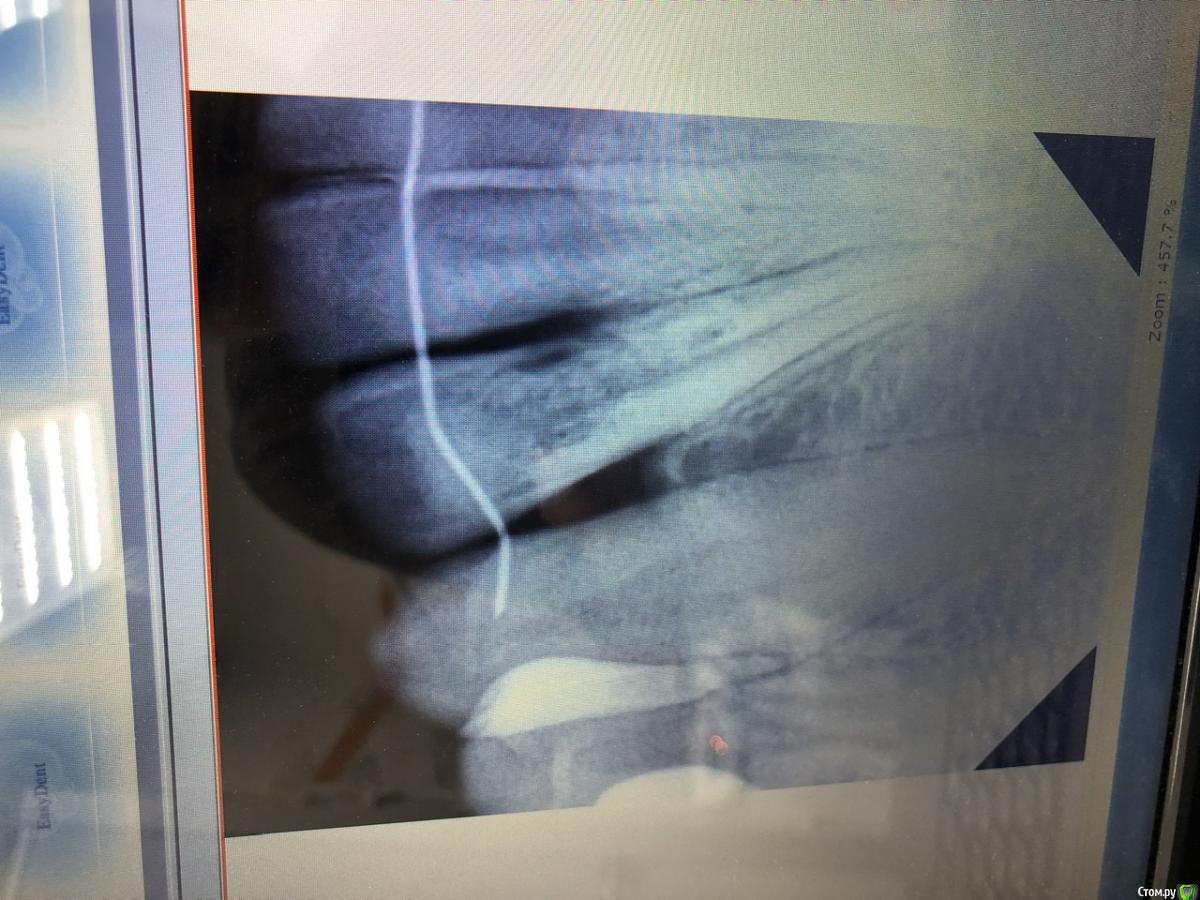

В июне 2019 года обнаружилась цервикальная резорбция двух нижних двоек. Полгода ушло на поиски врачей, вроде нашла, но сейчас немного сомнении, есть ли у нас шансы? Была в клиниках двадцати, две взялись именно лечить, выбрала ту, где было более внимательное и детальное обследование.

Ранее, в октябре 2017 обнаружена корневая резорбция нескольких передних верхних зубов, долго обследовалась и консультировалась, в итоге их просто наблюдаем и установили ретейнеры. С 15 до 20 лет стояли брекеты, прикус неправильный и после лечения. Сейчас 33 года.

Вопроса два - есть ли шансы остаться со своими нижними зубами и могла ли цервикальная резорбция быть вызвана полосками для отбеливания Crest?